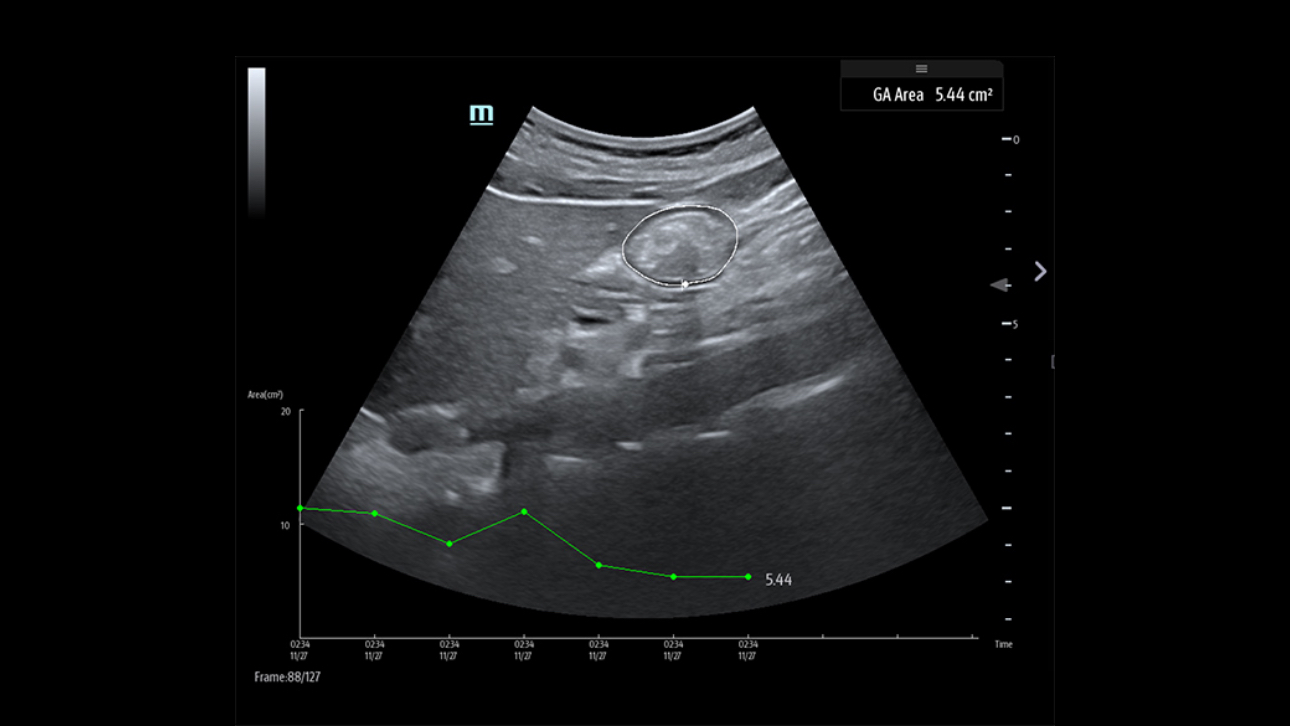

Aparat ultrasonograficzny TE9 zaprojektowano tak, aby rozszerzy? mo?liwo?ci diagnostyczne na oddzia?ach ratunkowych oraz intensywnej opieki. TE9 posiada wygodny i du?y ekran dotykowy oraz zaawansowane funkcje, kt├│re wspieraj? diagnostyk?. Inteligentne aplikacje kliniczne u?atwiaj? wykonywanie pomiar├│w, co pozwala sprawnie przeprowadza? badania i czynno?ci nawet w dynamicznym ?rodowisku pracy.

Obrazy kliniczne